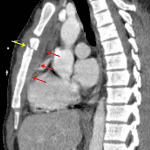

Sample ReportAcute oblique upper sternal body fracture with slight offset and a subjacent mediastinal hematoma measuring 1.5 cm in anteroposterior thickness. No direct evidence of aortic trauma or active hemorrhage.